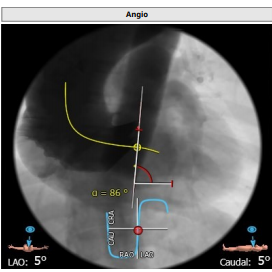

第一枪造影

这周谈谈我们手术中发现的一个比较罕见的现象,瓣叶切割,目前暂未见文献报道。瓣叶切割我们定义为特硬导丝或球囊,输送系统,破坏了瓣叶的原本结构,把原本完整的瓣叶切割裂开,从而导致瓣上结构的锚定力丧失。瓣叶切割常常发生在大弯侧瓣叶钙化重的情况下,横位心,条状钙化或钙化分布不均匀,联合部钙化融合等也是危险因素。DSA上通常是发现在交换特硬导丝后,或者球囊预扩张后,轨道位置发生明显的位移,此时结合食道超声,可以明确诊断瓣叶切割。瓣叶切割有利有弊。对于二叶瓣的病人,多数会改变瓣上结构的锚定力,比如type0二叶瓣变成类似三叶瓣结构,此时我们常用的downsize策略,高位释放策略需要重新考量。特别是高位释放,因为大弯侧瓣叶撕开,失去锚定力,高位释放容易发生瓣膜飞脱。对于部分三叶瓣的病人,瓣叶切割后导丝嵌入到钙化中心,会明显增加跨瓣难度,相对来说,瓣膜释放过程反而会比较稳定,不容易下滑。

此例患者大横位Type0型二叶瓣,瓣环径23.1,LVOT22.6,Stj35.9,左冠高度11.8,右冠19.5,术前根据总体结构使用20MM球囊预扩,抓捕器辅助瓣膜通过横位结构跨瓣,术前预装VenusA23号瓣膜。